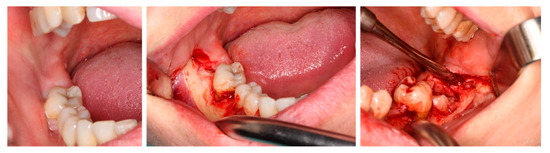

2.4. Surgical Procedure